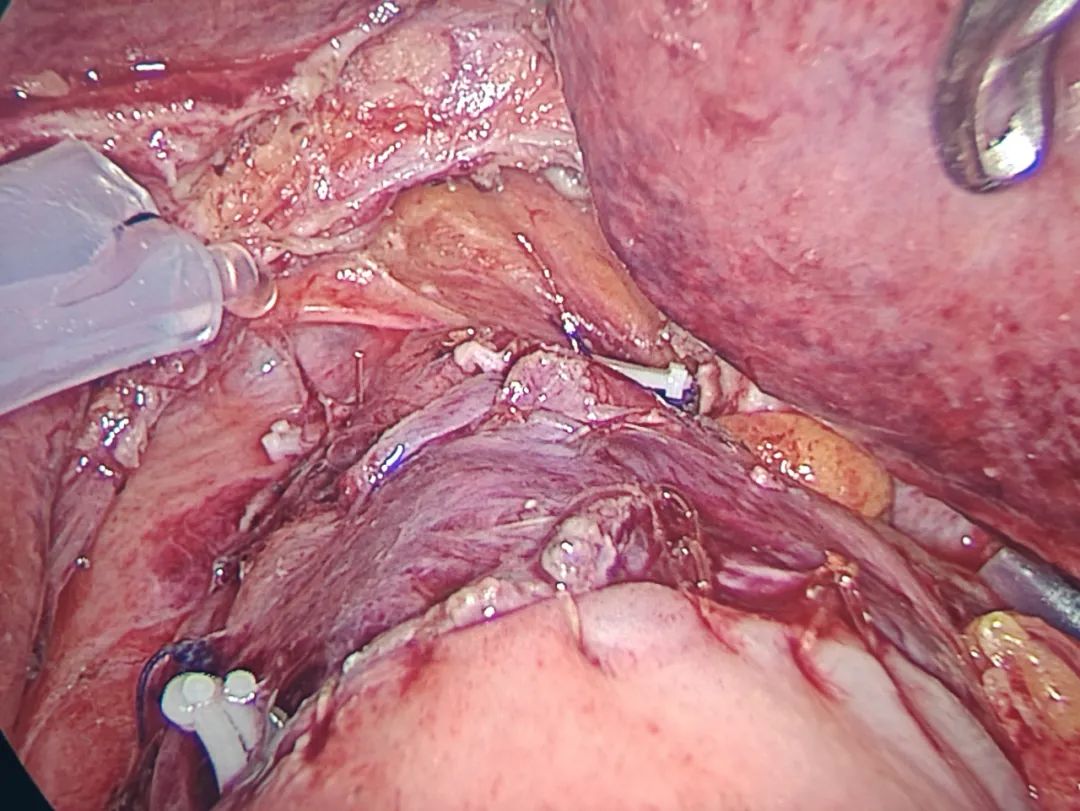

科室團(tuán)隊(duì)針對(duì)吳奶奶的病情開展了疑難危重病例討論,制定嚴(yán)謹(jǐn)、規(guī)范的手術(shù)——腹腔鏡輔助胃癌根治術(shù)(Kamikawa吻合)。黃賢強(qiáng)主任帶領(lǐng)團(tuán)隊(duì)精細(xì)操作,順利完成手術(shù)。

? ??

(食管胃雙肌瓣吻合)